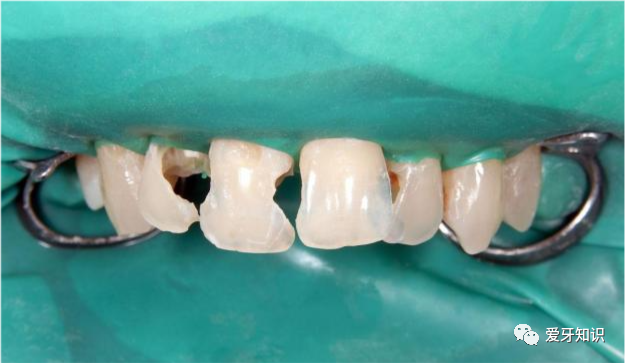

残冠残根

残冠残根,能保留就保留。就目前的医疗技术而言,做根管治疗后柱冠修复可以很好地将残冠残根保留下来。

残根残冠的存在,能够减缓牙槽骨的吸收,保持牙槽骨的高度,保留牙列的完整性。

但并不是所有的残根残冠都要保留,需要经过医生判断后再决定。